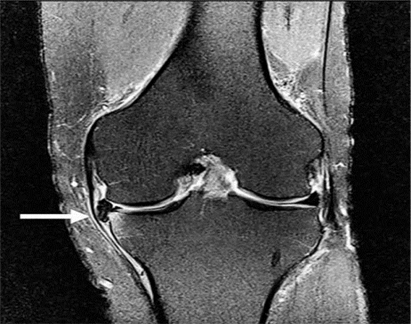

Hình 5. Vết rách ngang sụn với mảnh di lệch. Hình ảnh pd xóa mỡ với vết rách sụn chêm giữa và mảnh di lệch (mũi tên) nằm giữa dây chằng chéo giữa và mâm chày giữa.